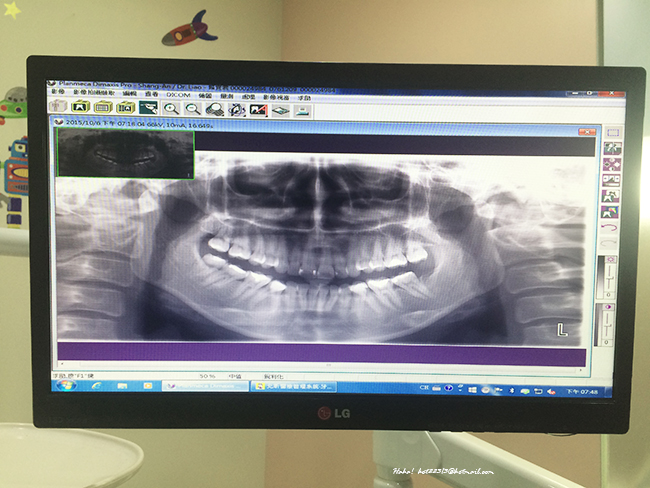

第一步驟:全景X光機 幫牙齒照X光

需確認是不是有深層的蛀牙

全景X光照出來啦~牙齒上方較白部分是補牙的地方

太害羞~牙齒一覽無遺的被照出來~幾乎每科都有補過呀~><

不過醫生說我牙齒目前蛀牙都補得很乾淨~嘿嘿嘿